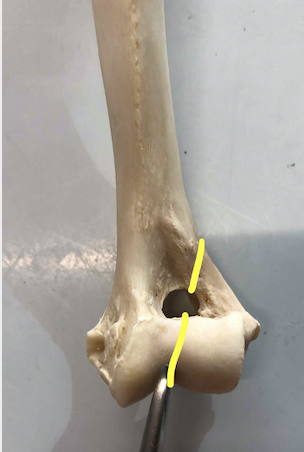

これが左の上腕骨を前方からみた写真です。

下の、黄色い線の部分で折れてしまったのが今回の骨折です。